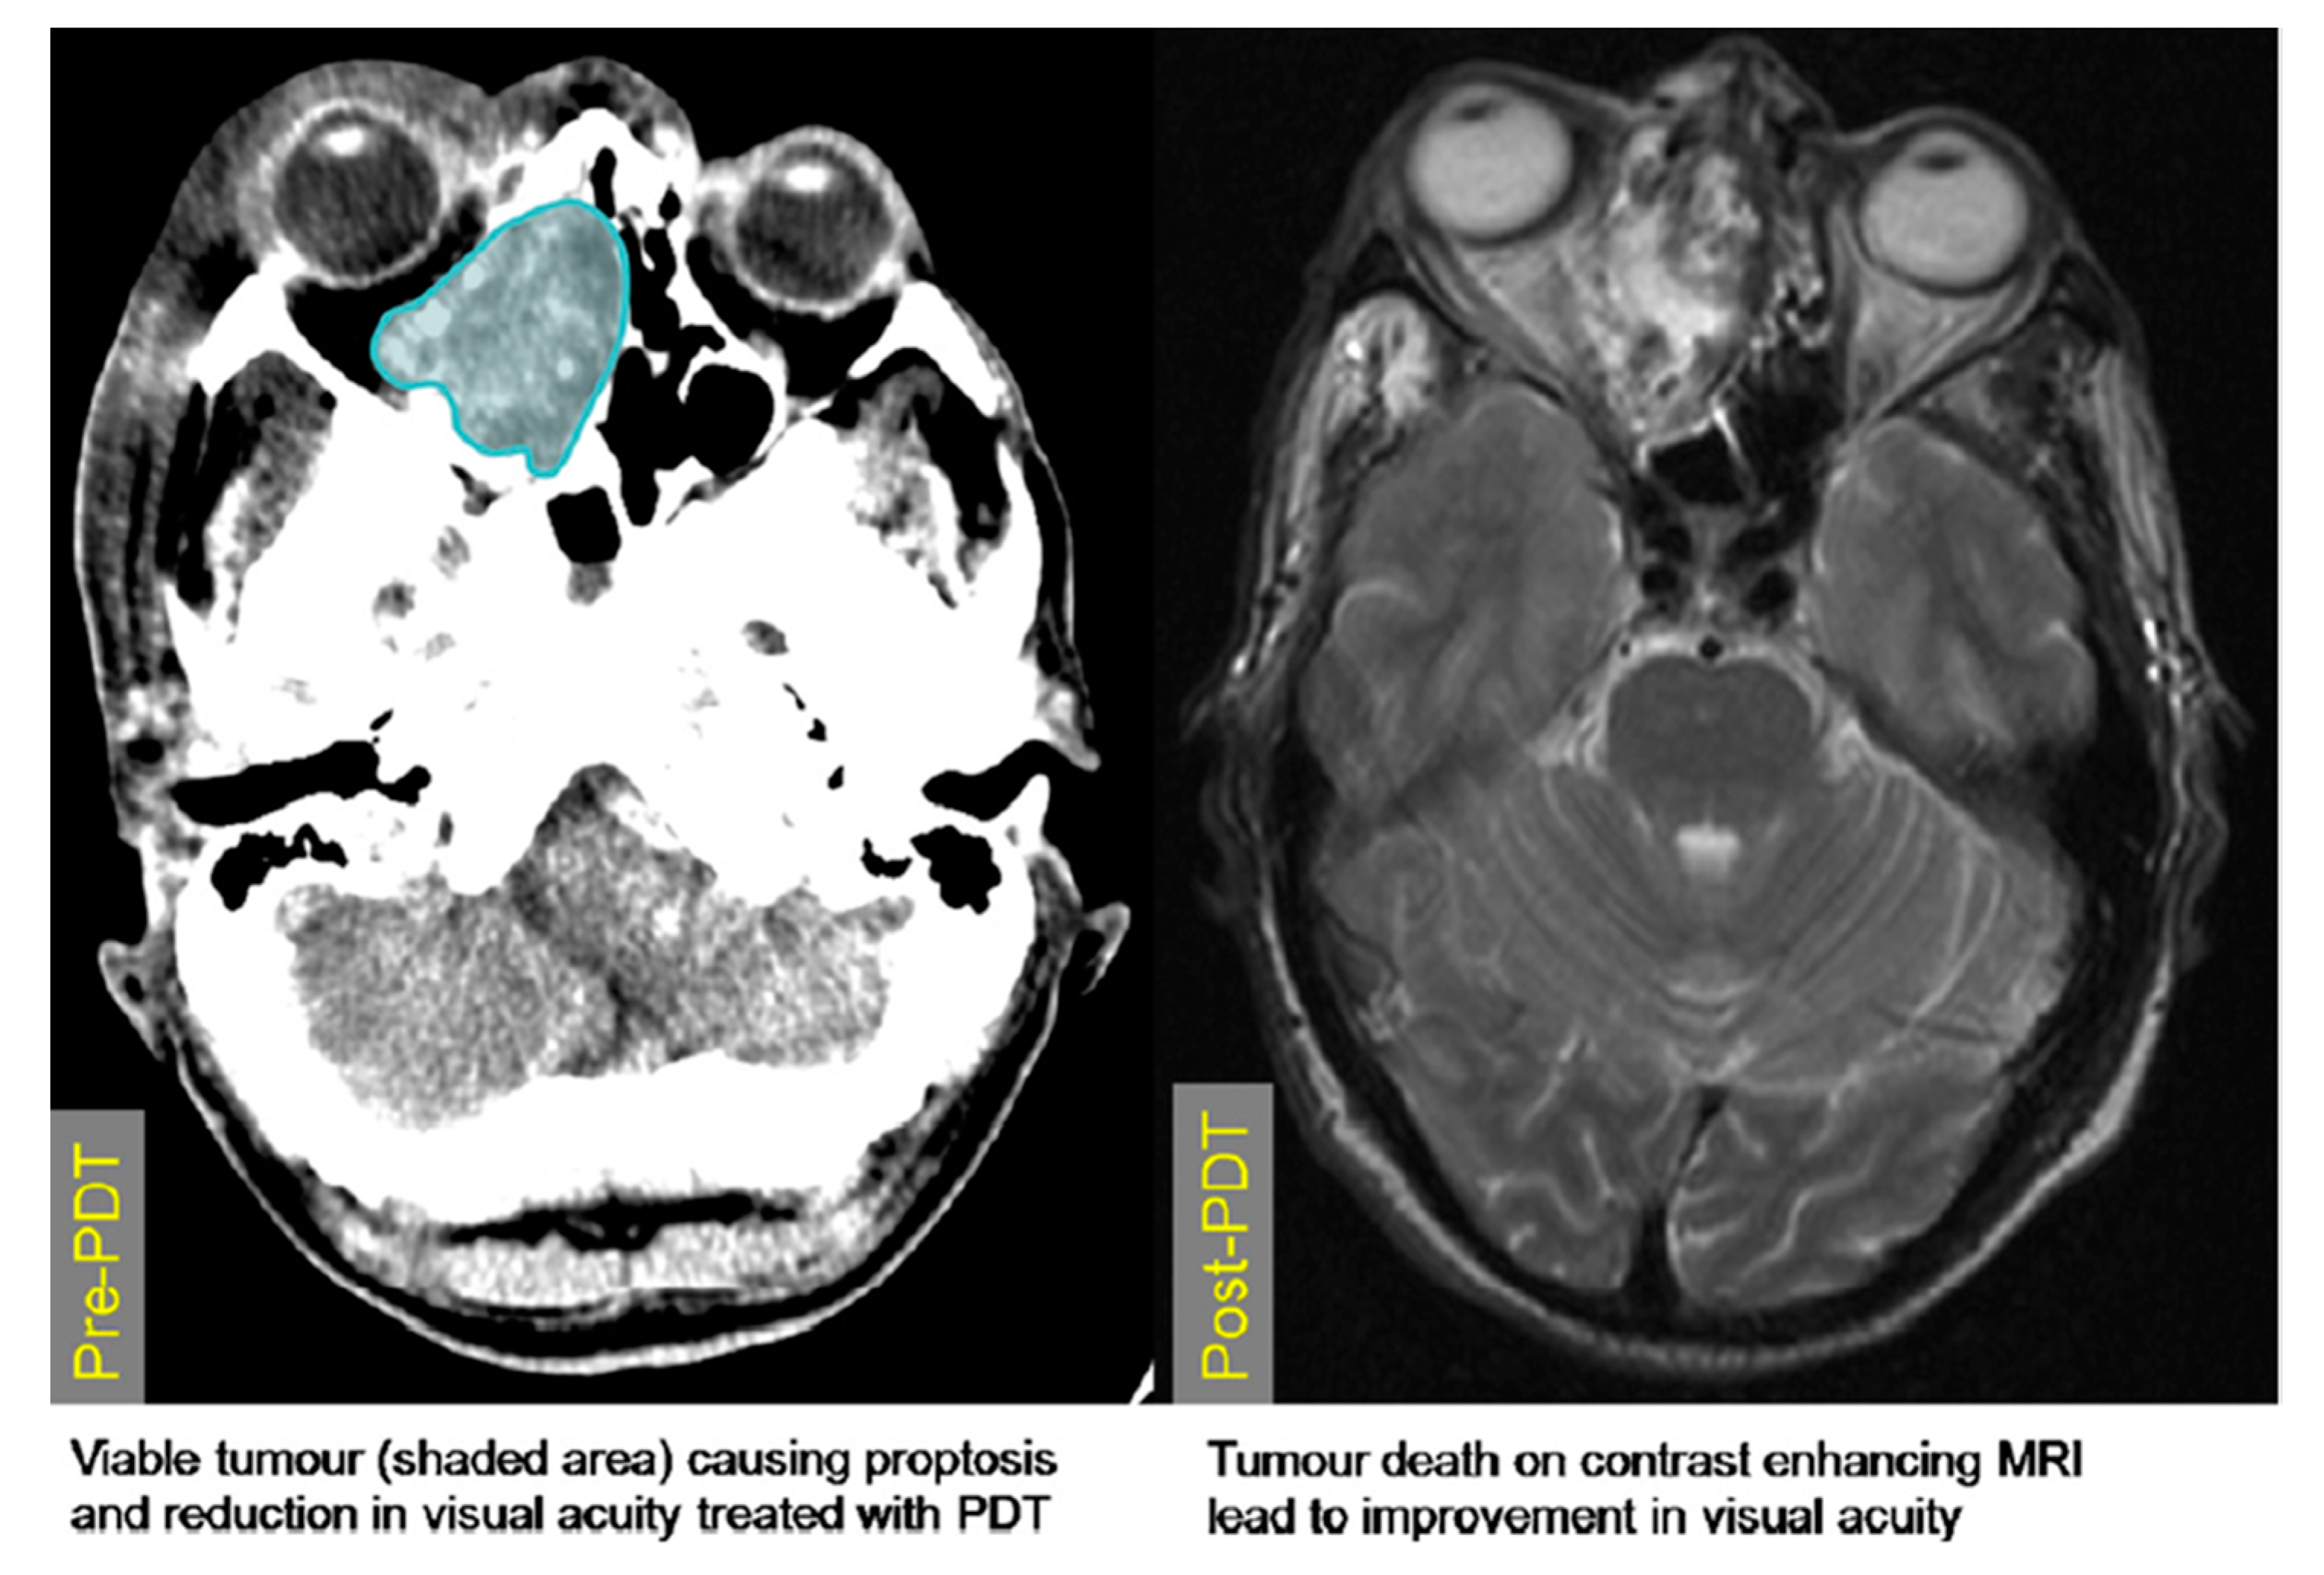

- Hamdoon, Z.; Jerjes, W.; Upile, T.; Akram, S.; Hopper, C. Metastatic renal cell carcinoma to the orofacial region: A novel method to alleviate symptoms and control disease progression. Photodiagn. Photodyn. Ther. 2010, 7, 246–250. [Google Scholar] [CrossRef]